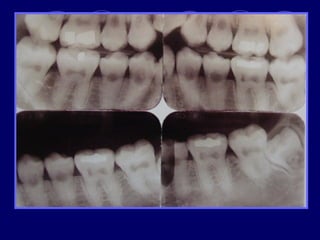

 Rx: falta de contacto entre dentina, esmalte

AMELOGENESIS IMPERFECTA  Hipoplásico: Zonas ausentes de esmalte  Afecta más a caras vestibulares  Esmalte: blanco amarillento y marrón claro, consistencia dura, fosas y surcos oscuras, delgado  Hipocalcificado:  Cualitativo  Esmalte frágil, fácil de desprender  Rx: falta de contacto entre dentina, esmalte  Hipomaduro:  Disminución en el contenido mineral  Esmalte blando y rugoso, veteado de blanco a marrón (esmalte en copos de nieve)  Más frecuente en caras vestibulares y dientes superiores